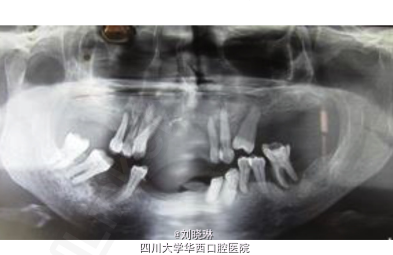

患者发现自己上前牙区逐渐肿大4年,其余病史无特殊。

检查发现患者上颌双侧尖牙之间可见一肿胀,约8cm*6cm大小,无蒂,无搏动,

术前组织活检结果显示为牙源性钙化上皮瘤。拟手术扩大范围切除。